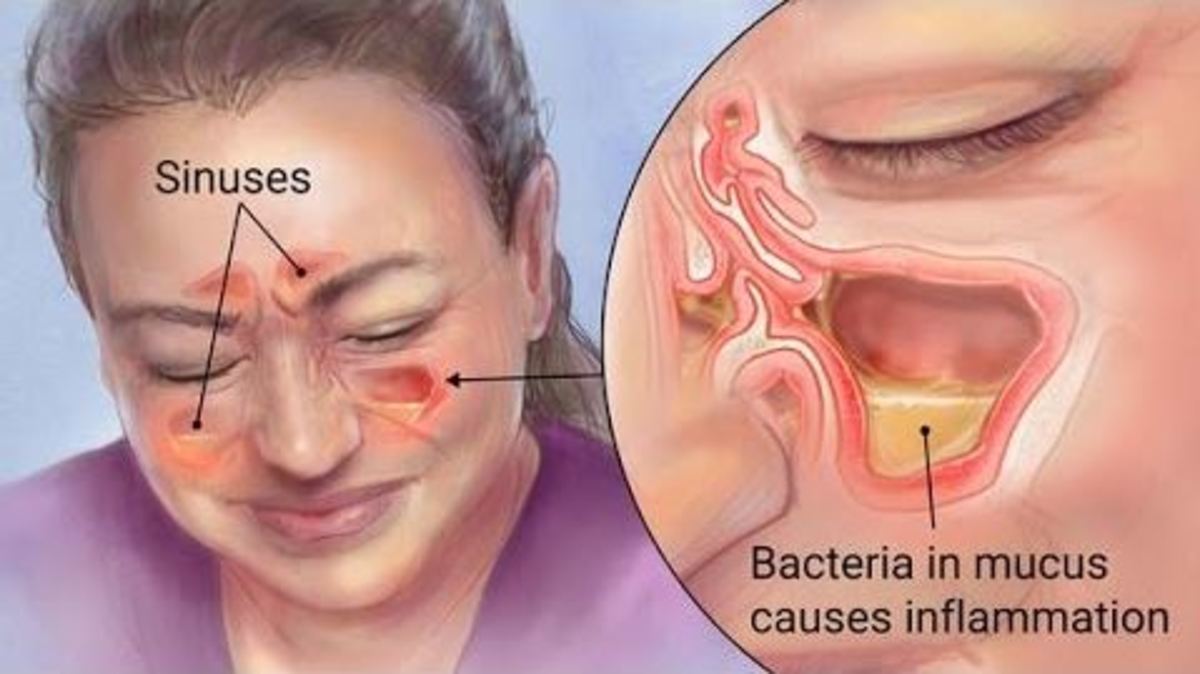

Ιγμορίτιδα είναι η φλεγμονή των ιγμορείων που ακολουθεί συνήθως κάποιο κοινό κρυολόγημα, γρίπη η κρίση αλλεργικής ρινίτιδας, με έντονο οίδημα του ρινικού βλεννογόνου και αυξημένη παραγωγή βλέννας.

Στην ιγμορίτιδα, το οίδημα αυτό προκαλεί απόφραξη των μικρών αγωγών που συνδέουν την μύτη με τα ιγμόρεια με αποτέλεσμα την αδυναμία παροχέτευσης αυτών με συνέπεια την εμφάνιση πόνου στο πρόσωπο η το μέτωπο, ανάμεσα η πίσω από τα μάτια η ακόμα στα μάγουλα και τα επάνω δόντια.

Αριστερά: Ιγμόρια (sinuses), Δεξιά: Τα βακτήρια στην βλέννα προκαλούν φλεγμονή